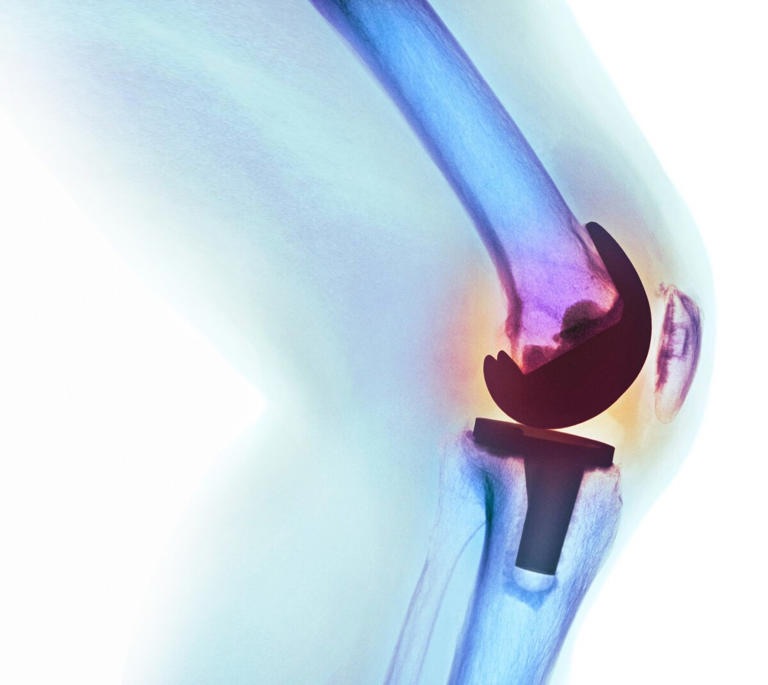

«Es una enfermedad crónico-degenrativa de todas las articulaciones: columna, cadera, rodilla, dedo, que se produce cuando el cartílago- que normalmente es un amortiguarddor dentro de las articulaciones- se va desgantando.

«Esto normalmente lleva a que el paciente presente dolor, rigidez y que ventualmente pierda le movimiento de la articulación afectada», explicó el especialista.